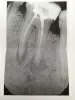

Зуб заболел в начале августа. Пошел к стоматологу. Врач сказала, что, скорее всего зуб под удаление, но решила попробовать спасти. Почистила каналы и положила лекарство. Зубная боль ушла через день. Так я проходил месяц с временной пломбой. Через месяц она вынула лекарство, опять почистила и начала пломбировать каналы, после чего сходил на рентген. По снимку она сказала, что улучшений нет, и зуб надо будет удалять. Оставила временную пломбу и дала еще с полмесяца времени с условием, что если разболится зуб, то будем удалять.

По данному рентгеновскому снимку есть воспалительный процесс за верхушками корней зуба и в области бифуркации, что является показанием к удалению зуба. Так как попытка эндодонтического лечения с кальцийсодержащим лекарственным препаратом не дала положительного результата и уменьшения очага воспаления.